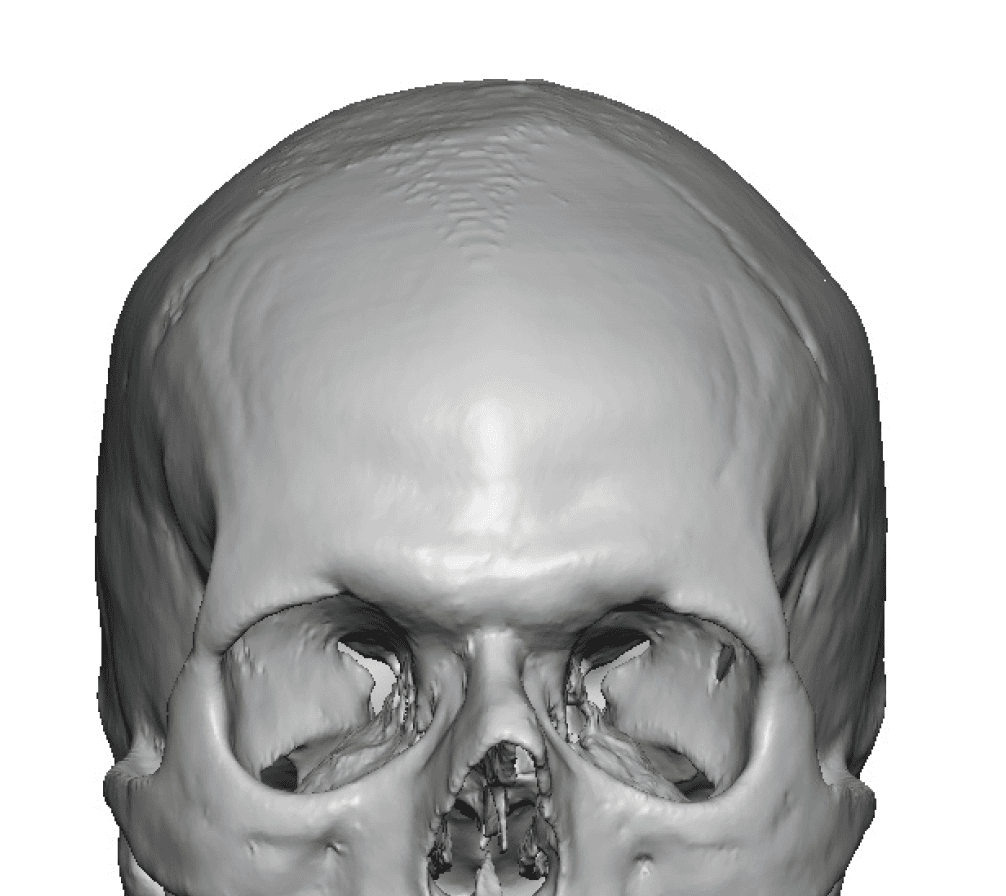

Patient 84

Desire for change of head shape from front view form an inverted V shape to a rounder and wider head shape.

Placement of custom extended forehead-temporal implants through incisions in the crease behind the ear. (he had a prior back of head skull implant which is green in the implant designs and which the head widening implants partially covered it)

Desire for change of head shape from front view form an inverted V shape to a rounder and wider head shape.

Placement of custom extended forehead-temporal implants through incisions in the crease behind the ear. (he had a prior back of head skull implant which is green in the implant designs and which the head widening implants partially covered it)